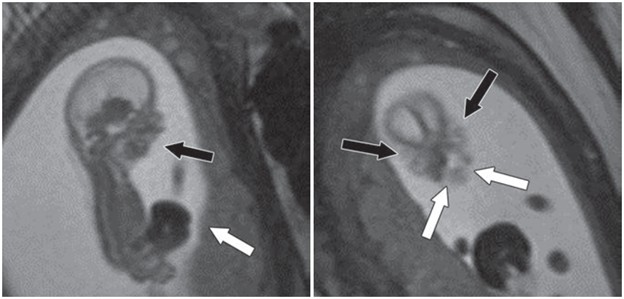

Fetus at gestational age of 13 weeks 0 days evaluated by MRI at 3T to characterize multiple congenital anomalies. Left, Sagittal 2D balanced SSFP image through entire fetus shows anterior abdominal wall defect with exteriorized liver (white arrow) and micrognathia (black arrow). Right, Coronal 2D balanced SSFP image through fetal face shows bilateral cleft lip and cleft palate (white arrows) and hypertelorism (black arrows). Additional anomalies depicted by this fetal MRI examination (not shown) included bilateral cerebral ventriculomegaly measuring 10–11 mm and severe dextroconvex thoracolumbar scoliosis. Umbilical cord length was normal, arguing against limb–body wall complex despite presence in this case of numerous typical diagnostic elements of this condition.